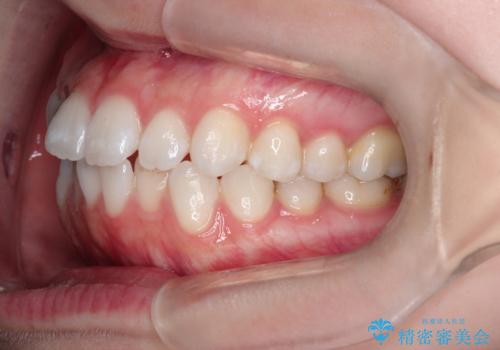

【インビザライン】がたつきをなおしたい

- 上下の前歯の凸凹が気になり、来院されました。

インビザラインで綺麗に仕上がり、満足していただきました。